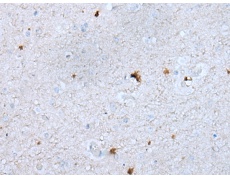

IHC positive control: |

Human brain |

IHC Recommend dilution: |

10-50 |